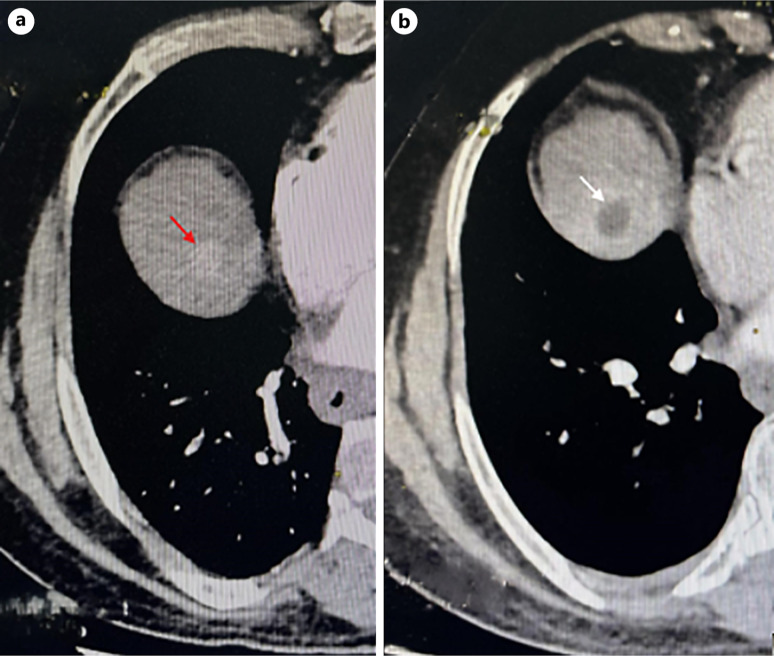

Case presentation: A 63-year-old male with compensated hepatitis B-related cirrhosis was under routine surveillance when a suspicious liver lesion was detected on ultrasound. Subsequent contrast-enhanced computed tomography (CT) confirmed the presence of an 18-mm HCC in segment VIII, corresponding to Barcelona Clinical Liver Cancer stage A. Due to limited curative treatment options, transarterial chemoembolization was considered. However, a follow-up CT scan was performed 2 weeks before the procedure unexpectedly revealed complete regression of arterial enhancement, suggestive of spontaneous tumor necrosis. The patient remained asymptomatic, with stable liver function and mild biological inflammatory markers. No evidence of vascular thrombosis or significant systemic inflammation was noted, suggesting localized vascular disturbances or intrinsic tumor factors might have precipitated the necrosis.